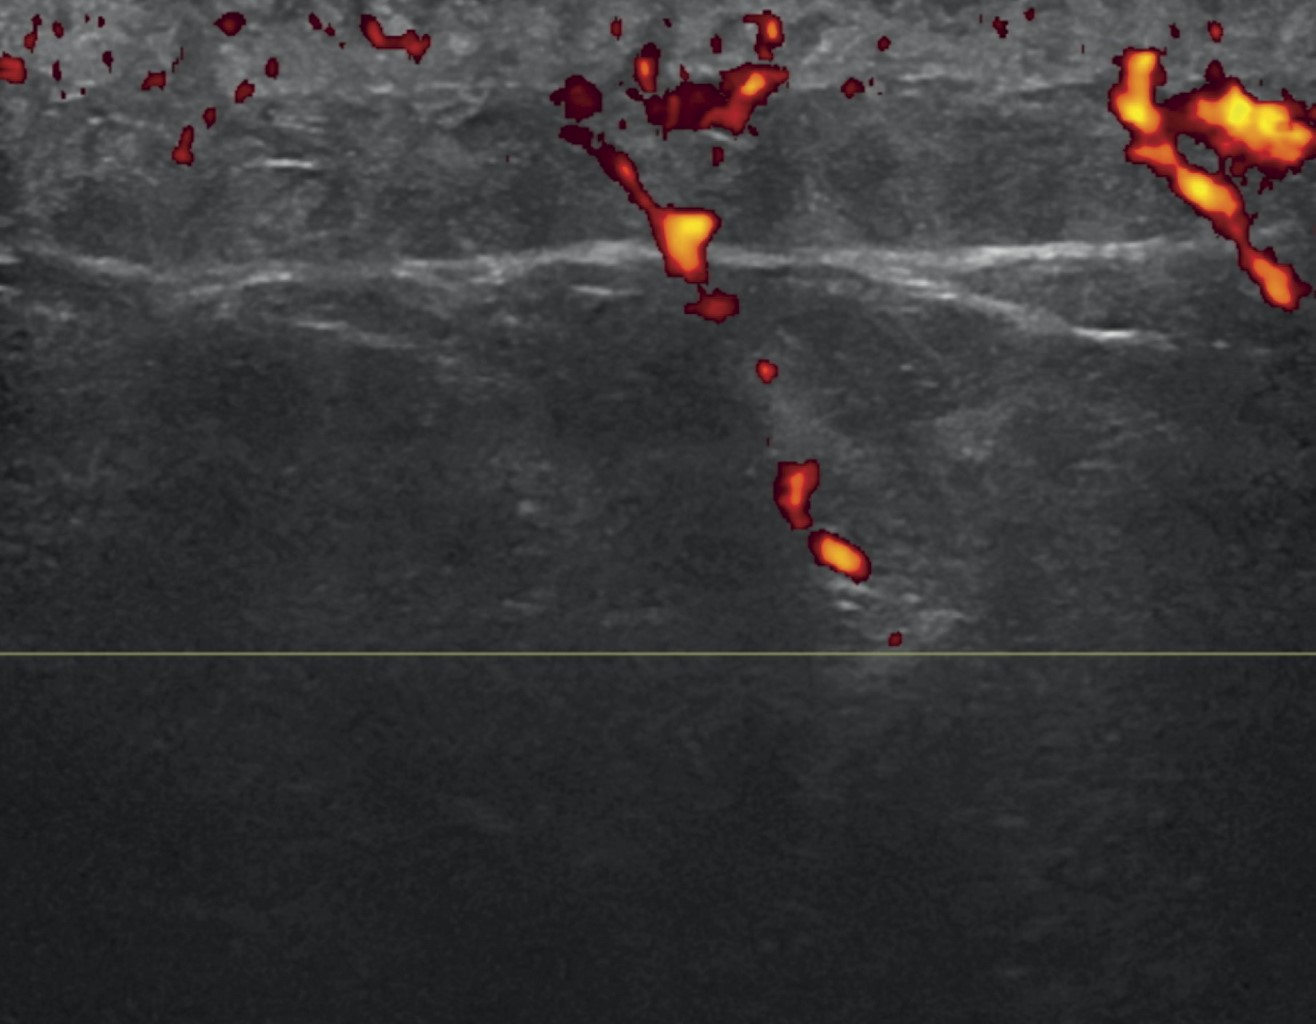

Figure 1

Figure 2

Figure 3

Figure 4

Figure 5